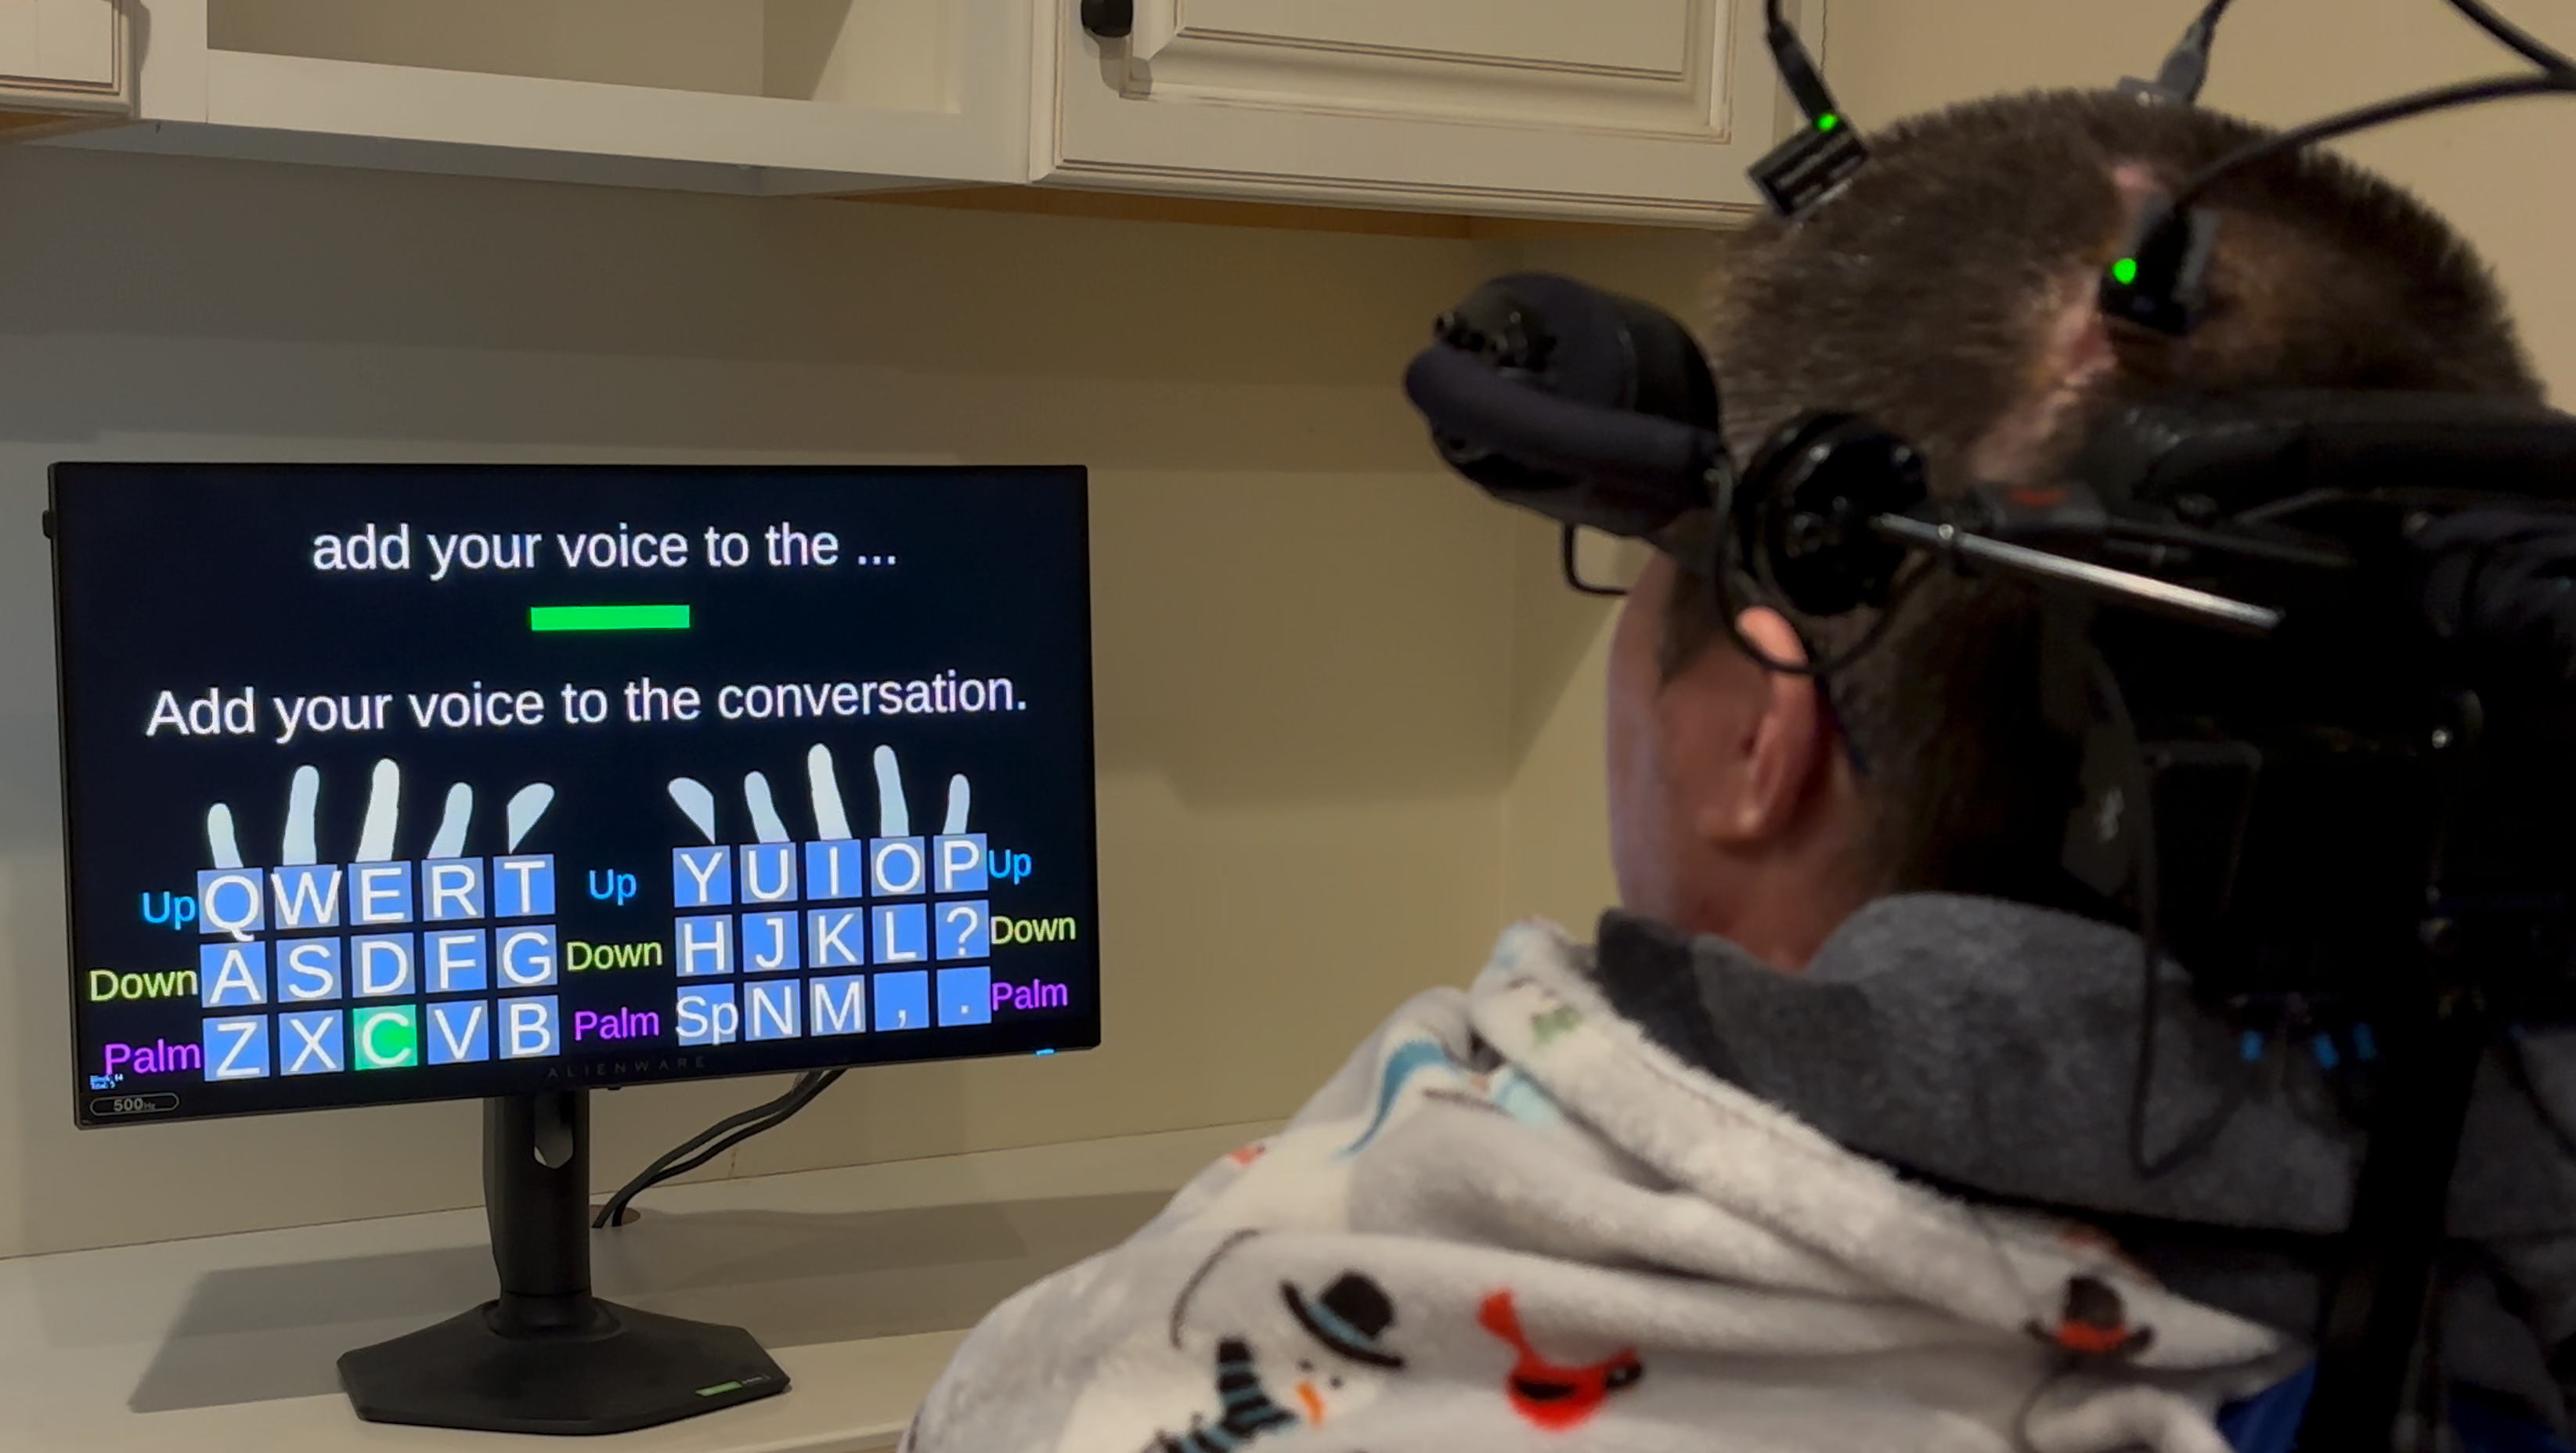

Brain implant allows people who are paralyzed to type using their thoughts at speed of texting

脑部植入物使瘫痪人士能够通过思维以短信速度打字

Brain implant allows people who are paralyzed to type using their thoughts at speed of texting

脑部植入物使瘫痪人士能够通过思维以短信速度打字

2026-03-16

925词 中等